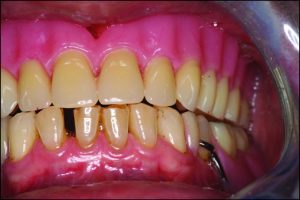

In bilateral balanced occlusion, during lateral movement, there are simultaneous bilateral contacts of opposing posterior teeth on both the working and balancing sides. For example, during a left lateral movement, antagonist tooth contacts occur on the working side primarily through the buccal cusps in the posterior region (Figure 9-4a), while on the opposite side, the buccal cusps of the mandibular teeth are in contact with the palatal cusps of the maxillary teeth. This prevents the right side of the removable prosthesis from lifting off the tissue (Figure 9-4b).

Figure 9-4. In bilateral balanced occlusion during left lateral movement:a) Antagonist tooth contacts on the working side occur through the buccal cusps.